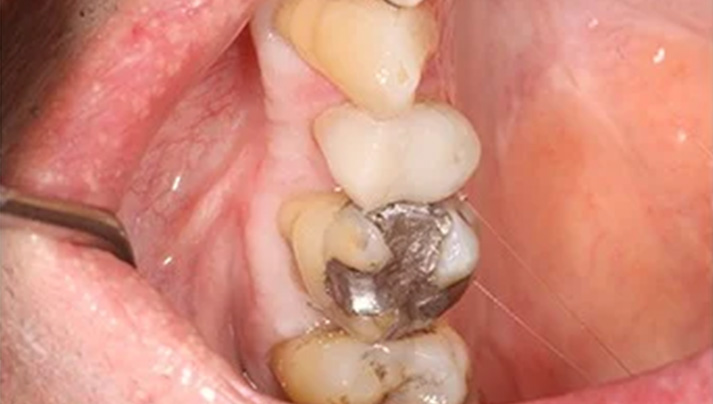

Before and Afters – White Fillings